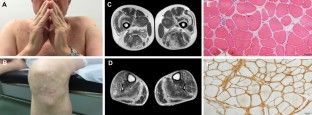

Fig. 1